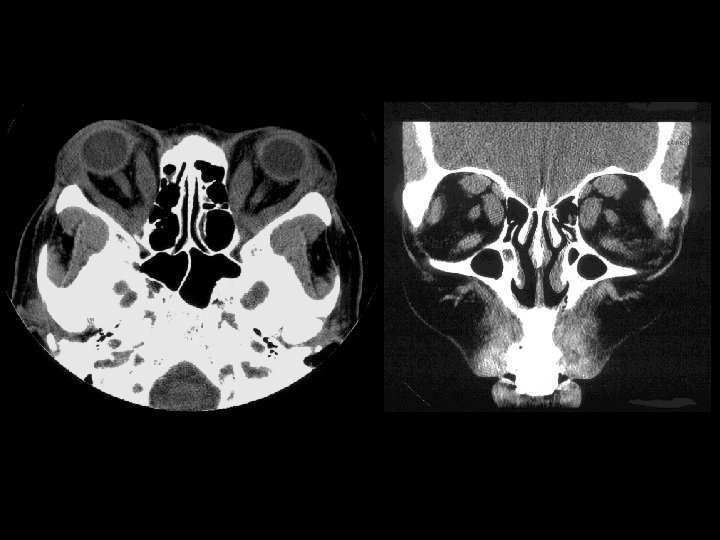

Thyroid opthalmopathy • Findings: – Bilateral enlargement of the extraoccular muscles except the lateral rectus = “I ’ M S L ow” – Sparing of the tendon – Usually NO eye pain • ddx: – Pseudotumor • Involves tendons • Pts have eye pain